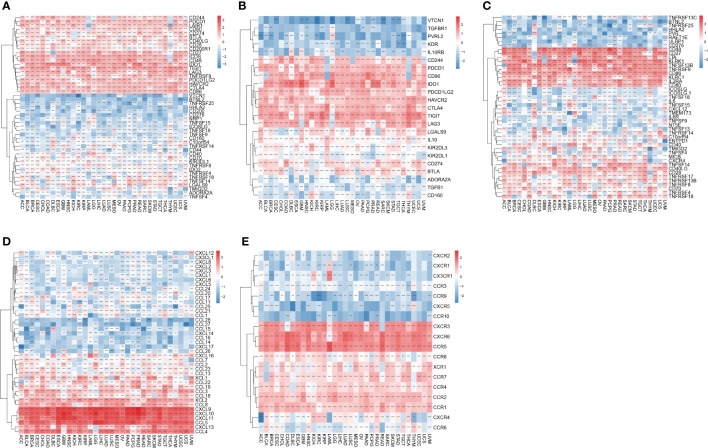

Association of IFN-γ score with genes involved in immunity